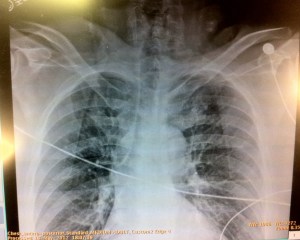

This was his lung view on the right:

The rest of his FAST scan was negative, and we knew right then and there – left sided PNEUMOTHORAX!!!! We ordered for supplemental oxygen, and, of course, had a bedside Chest XRay done to complete the trauma evaluation: